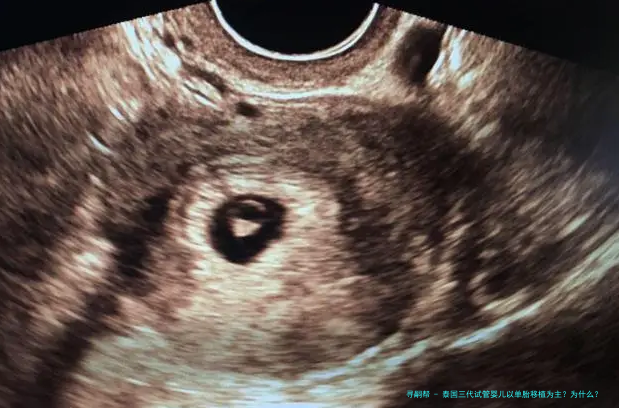

随着多个胎儿条件的放开,女年纪的增长,很多家庭去泰国做试管婴儿,因为要的是多胎,在进行胚胎移植的时候建议移植了一个胚胎。如此,泰国三代试管婴儿以单胞胎移植为主?为什么?下方跟随来一起了解一下吧。

泰国三代试管婴儿以单胎移植为主?为什么?

对于条件理想的患者,括移植2个有可能双胎妊娠的患者,或者因体重、子宫异常不能承受双胎妊娠的这么一部分患者,一般是建议进行单囊胚移植,既能保证她们的妊娠率,也能减低期的各种风险。

对于条件稍差的患者。比如:高龄、巢储备差,或者患子宫肌瘤、腺肌症等情况的患者,这些不利因素会影响胚胎着床率。那么,在这种情况下,会移植2个胚胎增加女方怀的机会。但,若是后期出现问题,从安全的因素考虑,请务必减胎。